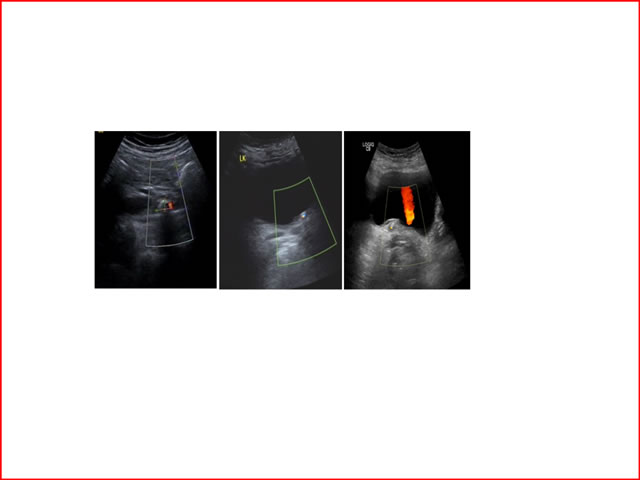

今天,我们回顾吕建林主任在多尼尔中国行——南京站暨ESWL超声定位科室交流会上的精彩演讲。他的演讲题目为:输尿管中下段结石超声定位ESWL。以下是他的讲课课件。

输尿管中下段结石超声定位ESWL